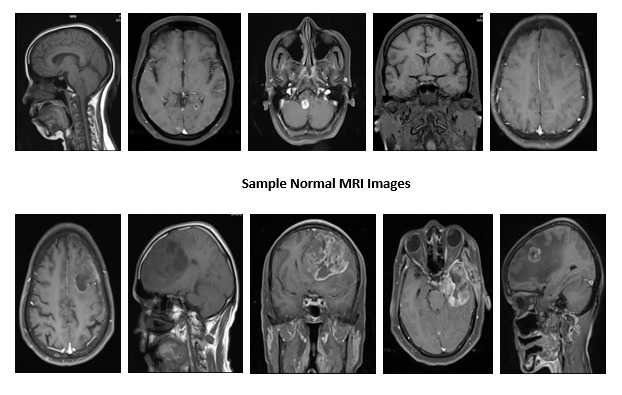

BRAMSIT – A New Dataset for Early diagnosis of BRAIN TUMOUR from MRI Images

In medical era the successful early diagnosis of brain tumours plays a major role in improving the treatment outcomes and patient survival. Most brain tumours are not diagnosed until after symptoms appear. Often, a brain tumor is initially diagnosed by an internist or a neurologist. Diagnosing a brain tumor usually begins with magnetic resonance imaging (MRI). Once MRI shows that there is a tumor in the brain, the most common way to determine the type of brain tumor is to look at the results from a sample of tissue after a biopsy or surgery. So it is obligatory to enclose a customary database in MRI images for the young bud researchers to capture up the dealings to the advance stage by accurate examination of the medical results of the images. 391 MRI images of different patients are collected and the database is created. The proposed MRI database, named as MRISIT, represents an initial attempt to provide a set of MRI scan images consisting of normal, abnormal along with its ground truth images of different axial (Sagittal, Coronal and Transaxial) position,